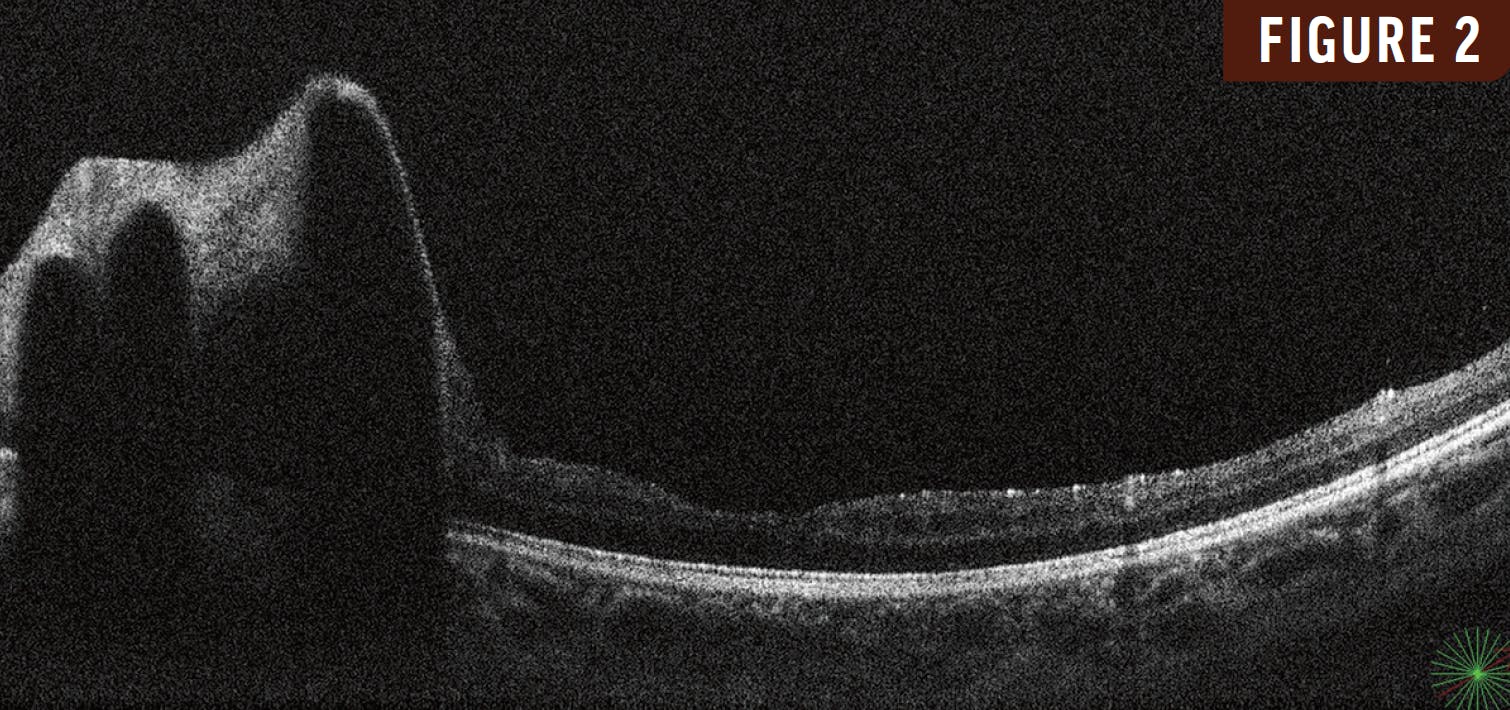

A 10-year-old girl presented with a 3-month history of reduced vision in her left eye. Her VA was 20/20 OD and 20/200 OS. Fundus examination of her left eye revealed markedly dilated, corkscrew-like arteriovenous channels with perivascular sheathing that extended from the optic disc into the superotemporal retina (Figure 1). OCT revealed large hyperreflective intraretinal vessels with posterior shadowing and a normal foveal contour (Figure 2). Fluorescein angiography revealed rapid filling of the arterial and venous components with minimal transit time with no associated leakage (Figure 3).

Based on these findings, the patient was diagnosed with racemose hemangioma in her left eye. Neuroimaging to rule out Wyburn Mason syndrome was negative.